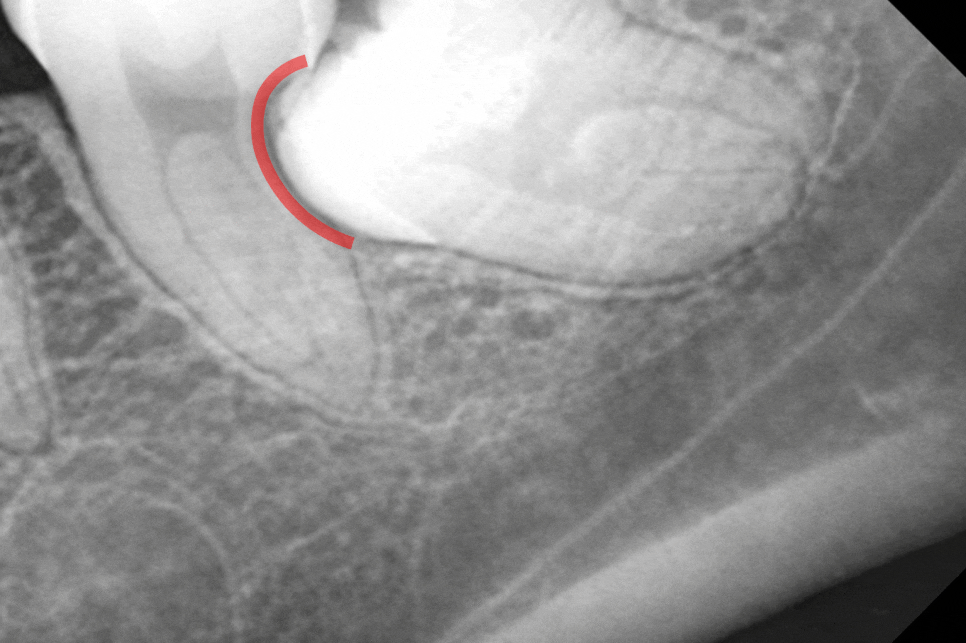

치조골 혹은 앞쪽 어금니의 치근을

지속적으로 압박하면서 생긴 압력과 더불어

치관주위염으로 인해 활성화된 파골세포는

치조골을 녹여버려 엑스레이에서

뼈가 검게 투과되어 보이는

골소실 양상이 나타납니다.

이는 치아를 지탱하는 뼈의 높이가

낮아졌음을 의미합니다.